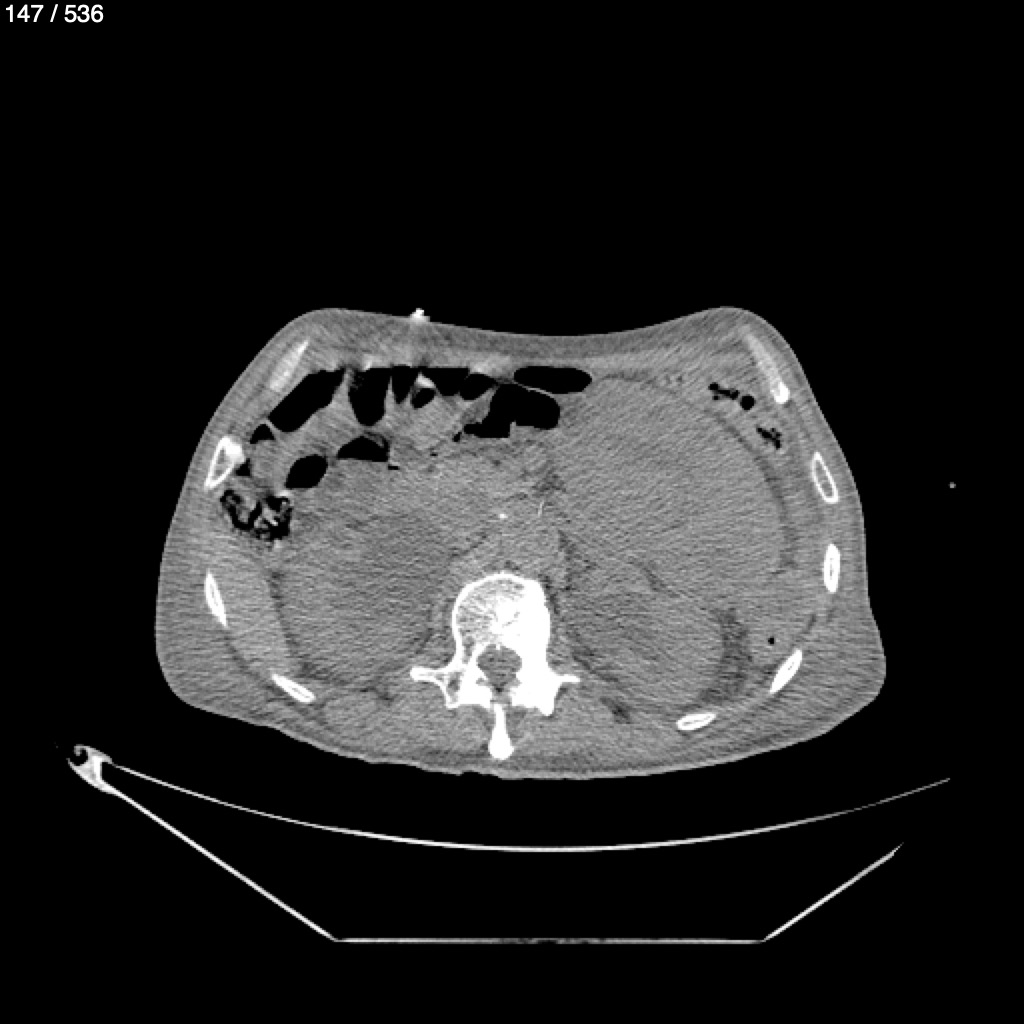

Angel Villalobos Palomeque 73 A - T.C Abdomen Simple